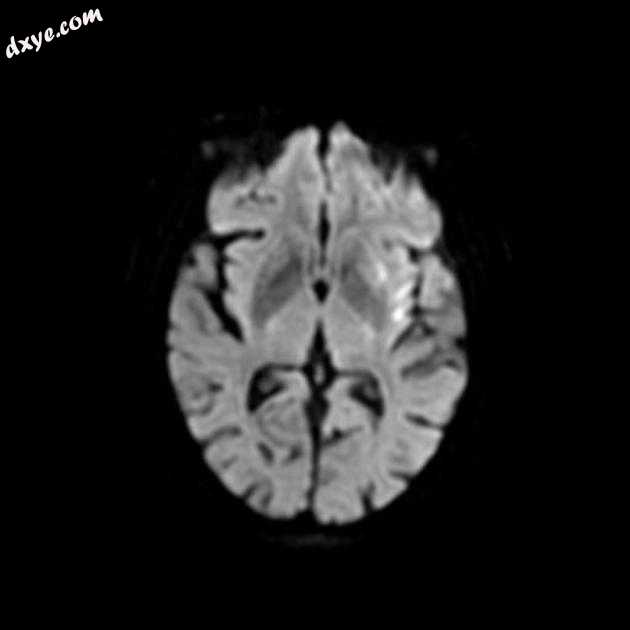

Axial DWI

MRI 序列显示左侧大脑中动脉 (MCA) 区域分布中的弥散受限区域,在 FLAIR 序列上不可见。在 GE 序列上没有看到出血性转化。 MRA 3D-TOF 显示左侧大脑中动脉完全闭塞。

早期超急性大脑中动脉 (MCA) 区域梗死的 MRI 特征。